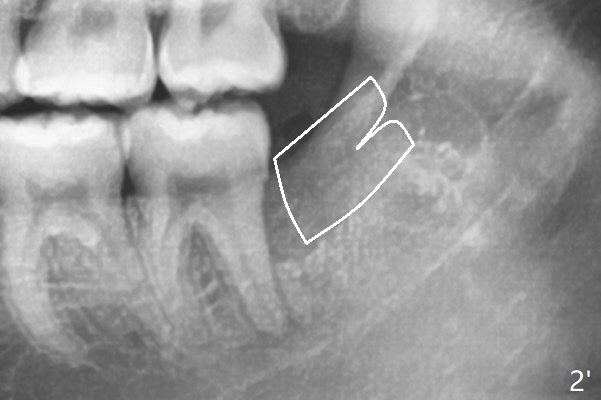

White outline is the orientation (horizontal) and relative position (as mesial as possible) of the Osteogen plug.  One end happens to have been cut.